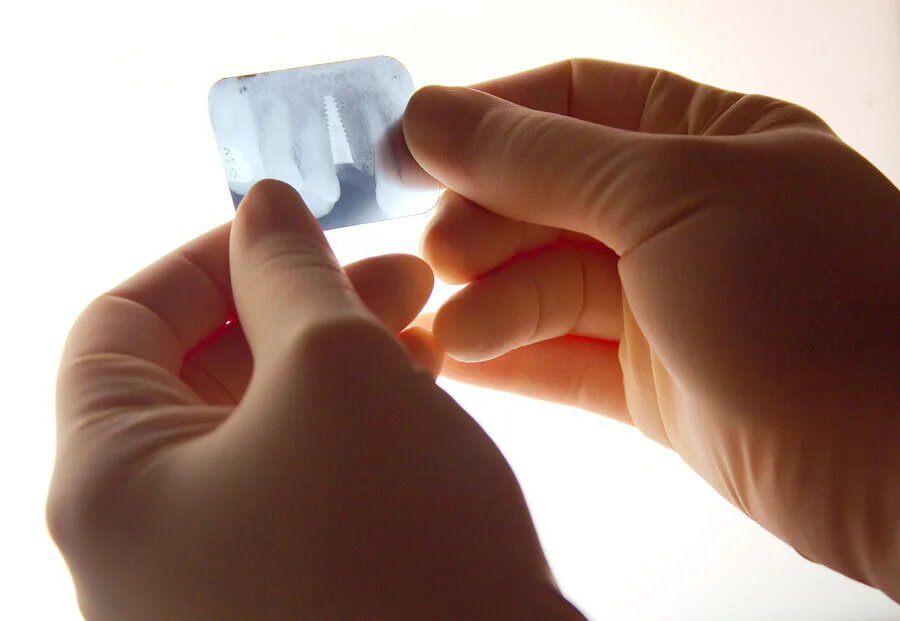

Röntgenstrahlen sind elektromagnetische Wellen von hoher Energie welche die verschiedenen Gewebeschichten durchdringen. Sie erzeugen so auf einem Film ein Schattenbild. Früher wurde dieses auf einem Fluoreszenzschirm angezeigt. In unserer Praxis verwenden wir digitale Röntgentechnologien.

Unter dem Begriff „Zahnimplantate“ versteht man das Einbringen eines körperfremden Materials in den Kieferknochen, das als Basis zum Ersetzen von fehlenden Zähnen dient. Dadurch werden die Voraussetzungen für die weiteren Rekonstruktionen der verlorenen Zähne geschaffen. Das bedeutet, dass an den Stellen, wo früher die natürlichen Zähne waren, die Zahnimplantate die Funktion der Zahnwurzeln übernehmen.